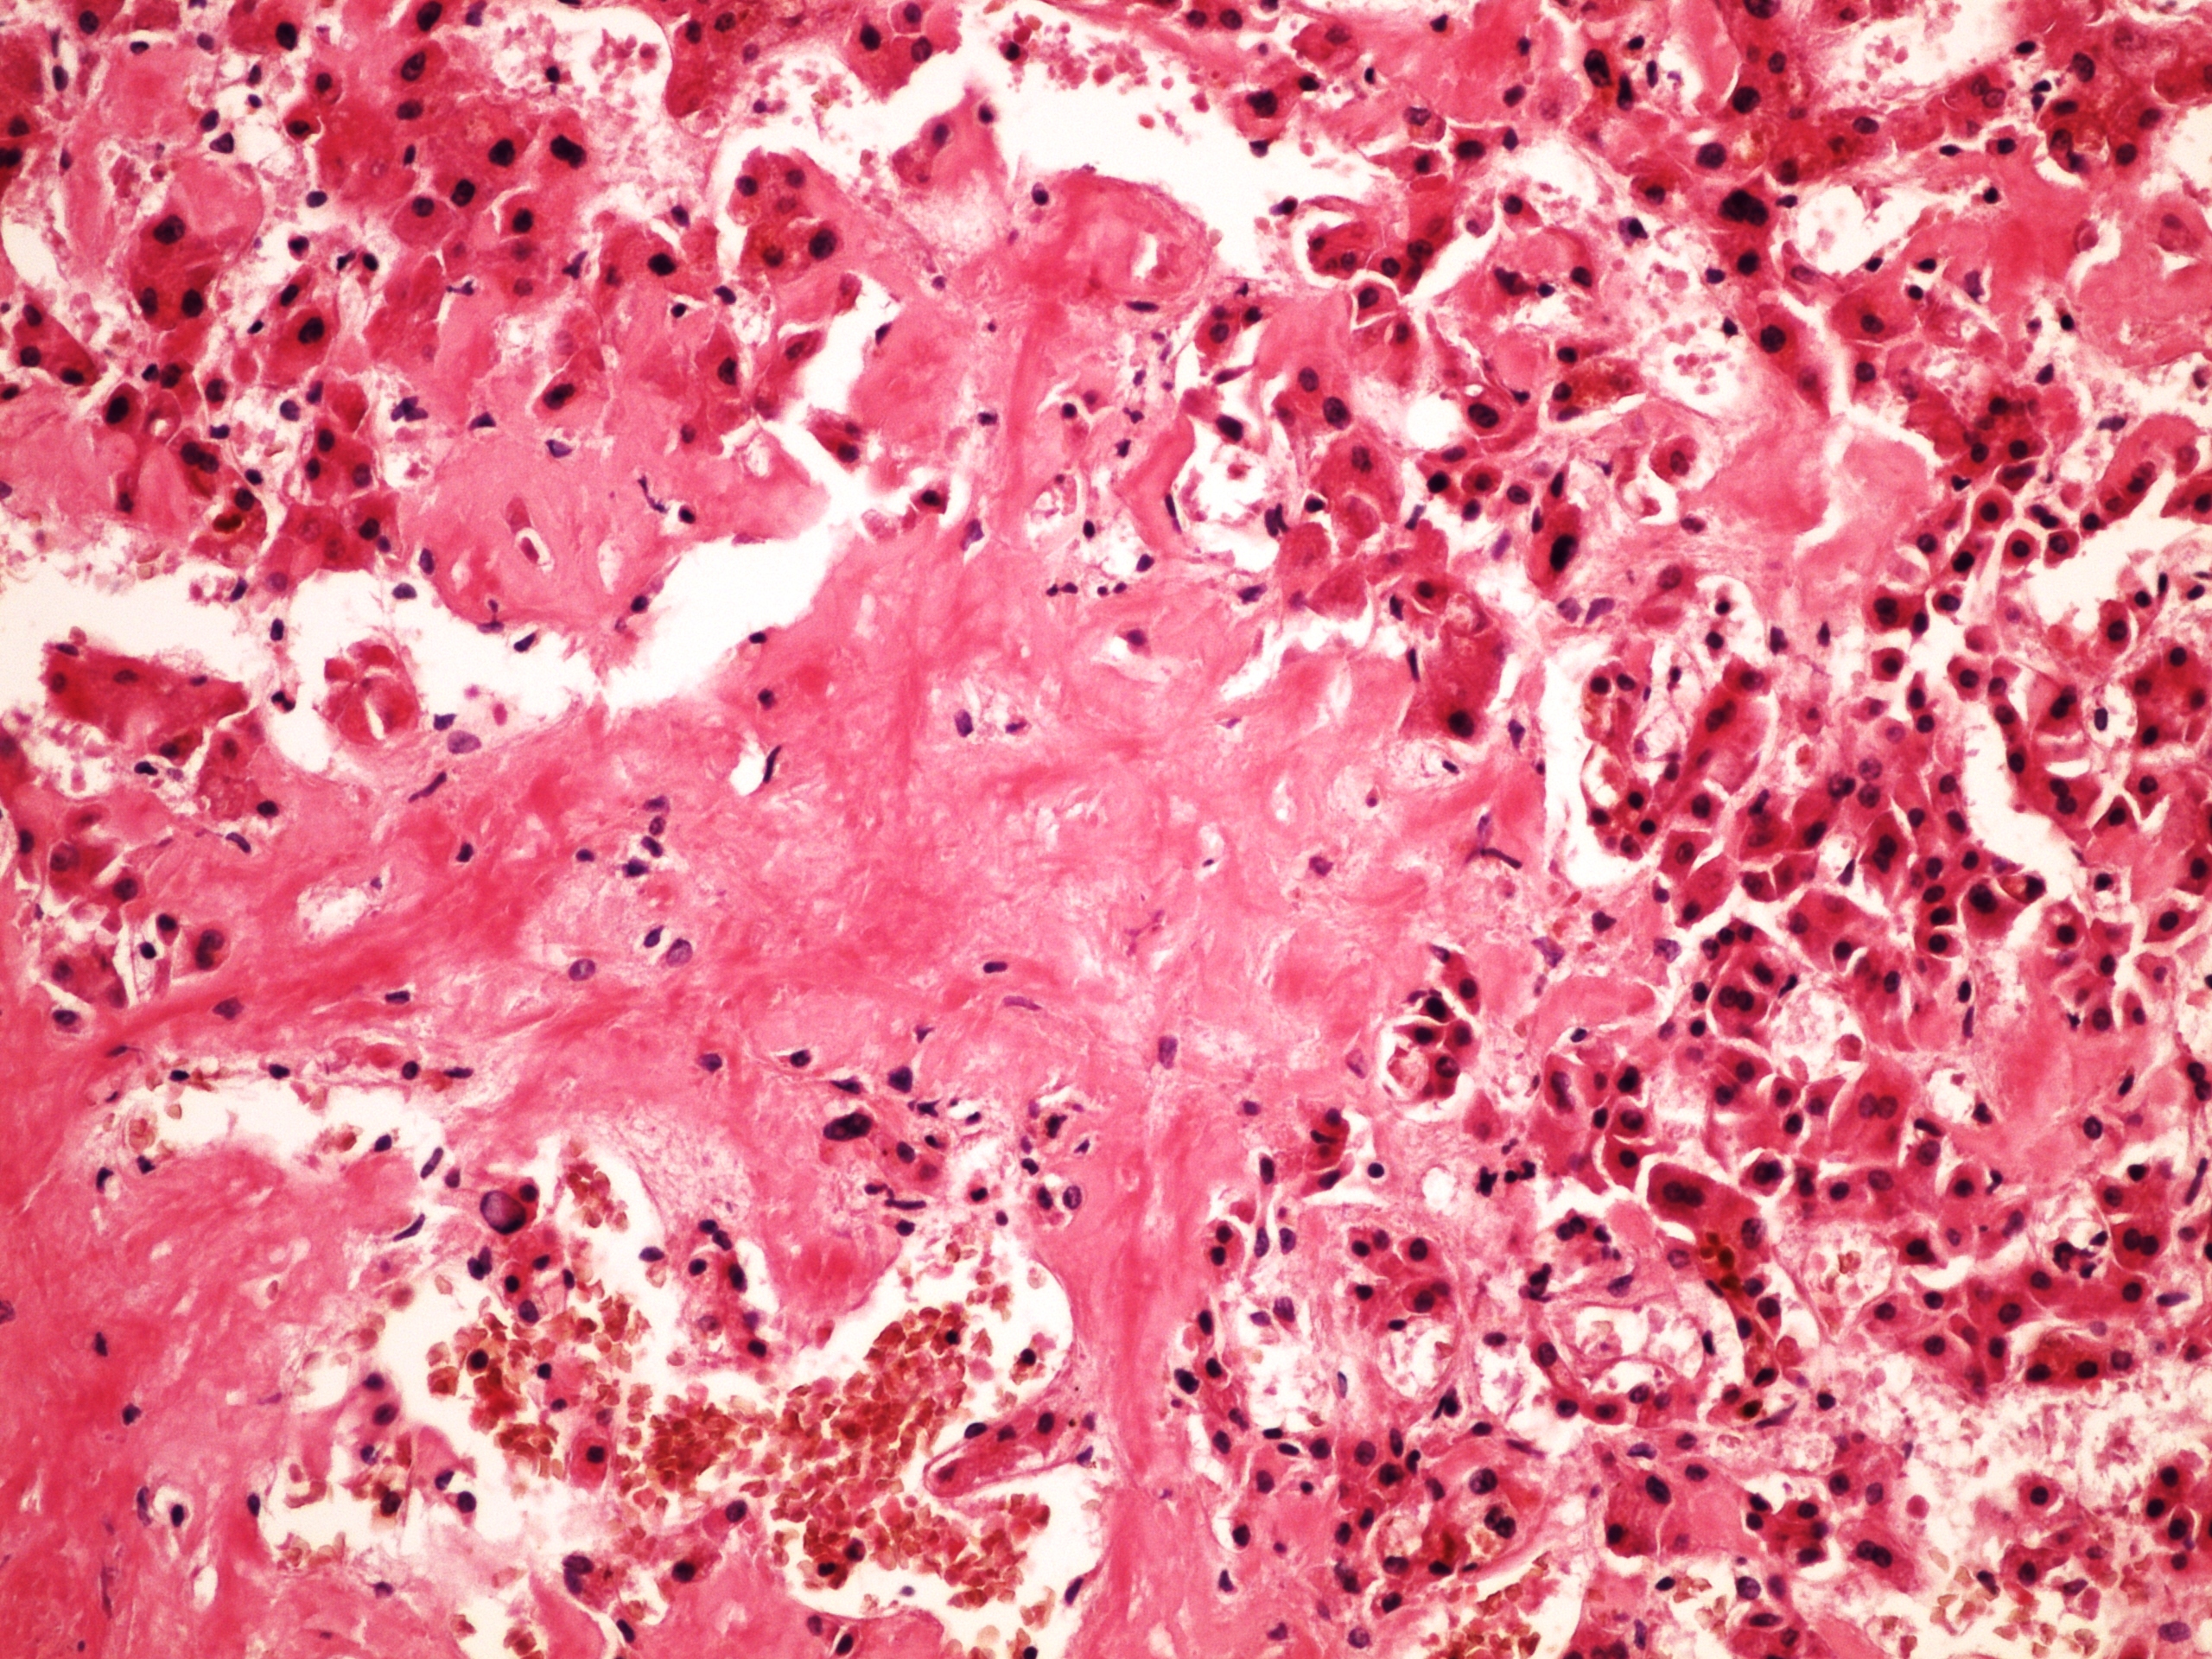

Макрофотографии жировой дистрофии почек